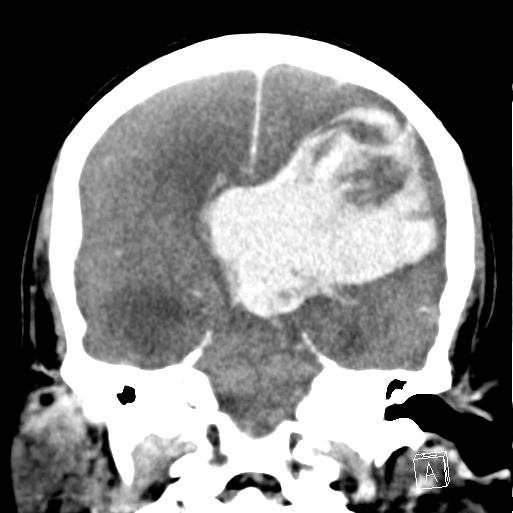

- Intracranial haemorrhage